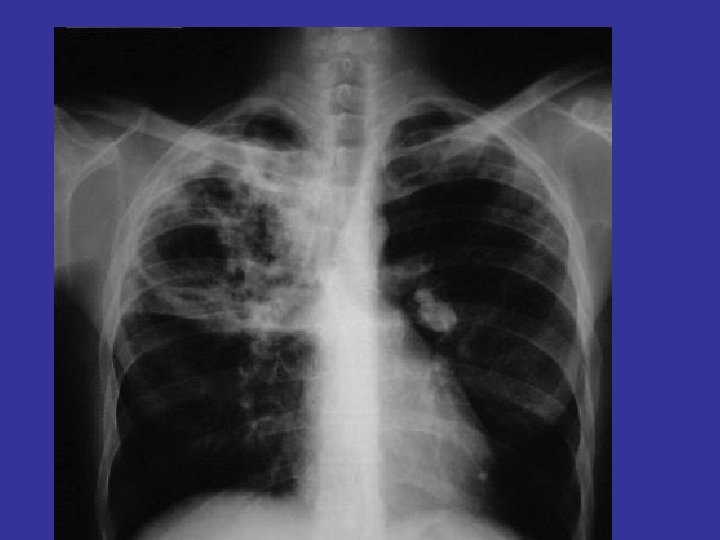

Secondary Tuberculosis: • Post Primary in immunized individuals. • Reactivation or Reinfection • Cavitary Granulomatous response. • Apical lobes or upper part of lower lobes – O 2 • Caseation, cavity - soft granuloma • Pulmonary or extra-pulmonary • Local or systemic spread / Miliary – Vein – via left ventricle to whole body – Artery – miliary spread within the lung

• 1° TB usually involves the middle or lower lung zones and is associated with hilar adenopathy (Gohn complex). • 2 ° TB represents reactivation and typically involves the upper lungs and cavitation. • regimen RIPE—Rifampin, Isoniazid (INH), Pyrazinamide, and Ethambutol daily for eight weeks, followed by INH and rifampin for an additional 16 weeks. Give vitamin B 6 to prevent INHassociated neuropathy.